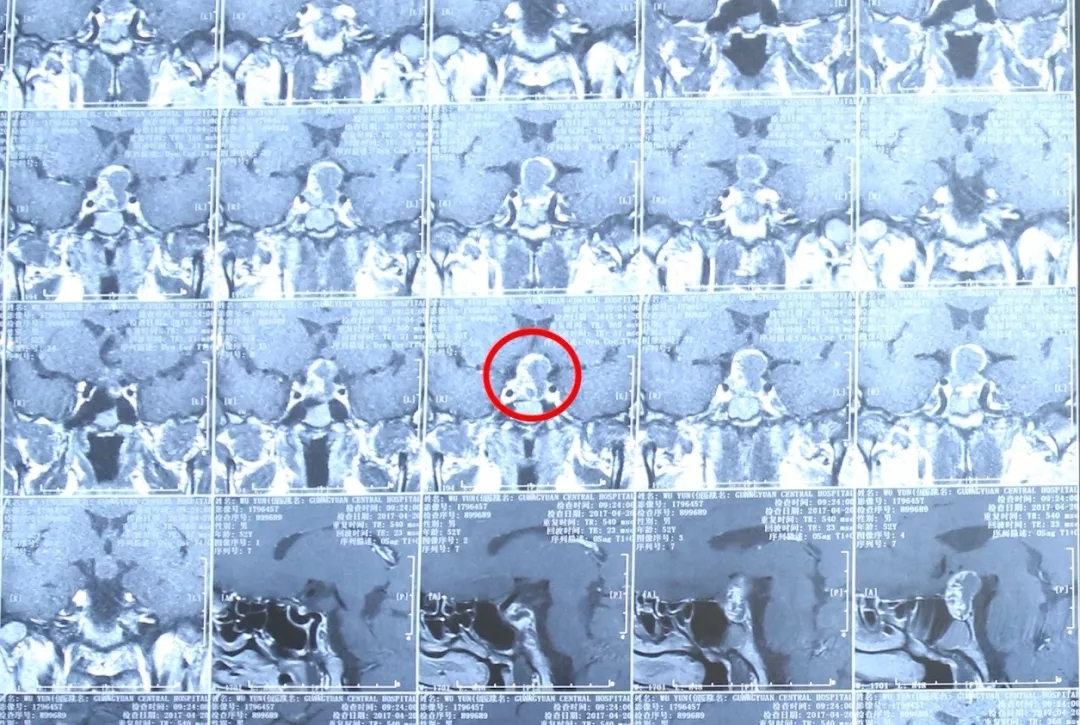

颅咽管瘤为先天性肿瘤,约占颅内肿瘤的5%。多见于儿童及少年,男性多于女性。临床常表现为颅内压增高、双侧视力减退、视野缺损、精神不振、嗜睡、记忆力减退、反应迟钝、思维混乱、多饮多尿等。

颅咽管瘤患者MRI